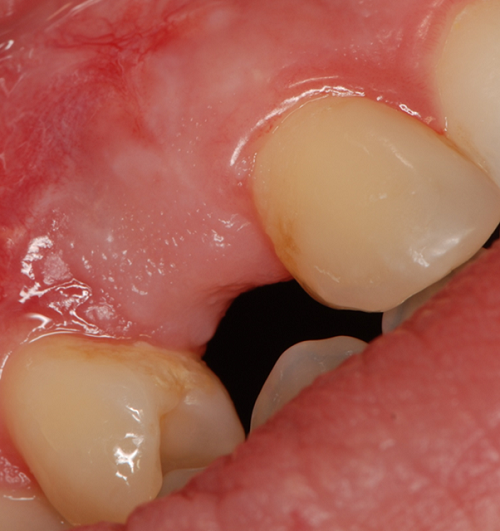

Streszczenie: W zabiegach implantacyjnych w strefie estetycznej szczęki ważną rolę odgrywa biotyp dziąsła, który wpływa na estetykę i zanik kości wokół implantu. Do pomiaru grubości dziąsła stosuje się metodę ultrasonografii, która jest nieinwazyjna i powtarzalna. W celu pogrubienia fenotypu dziąsła możliwe jest pobranie przeszczepu tkanki łącznej z podniebienia, w celu augmentacji tkanek miękkich. Metoda ta może jednak powodować dyskomfort pozabiegowy dla pacjenta. W artykule opisano kliniczny przypadek zastosowania fotobiomodulacji laserowej 635 nm do przyspieszenia gojenia się tkanek, zmniejszenia dolegliwości bólowych i poprawy adaptacji przeszczepu łącznotkankowego.

Summary: In implantation procedures in the aesthetic zone of the maxilla, an important role [...]